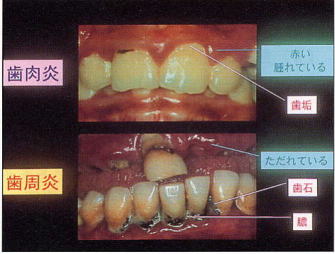

☆歯周病とは・・・

歯ぐきの発赤・腫脹・出血、排膿(膿が出ること)があり、口臭、歯の動揺(歯がぐらぐら動くこと)によって噛みにくくなり、そして、重症化すると歯が脱落する。

☆病気の重症度

・歯肉炎:歯ぐきのみの炎症(元に戻ります)

・歯周炎:歯を支えている組織(歯ぐき、歯を支えているじん帯、骨)まで炎症が進行(もとの状態には戻りませんが、進行を止めて歯周組織を維持することが必要です。)

※歯肉炎から歯周炎と状態が重症化します。